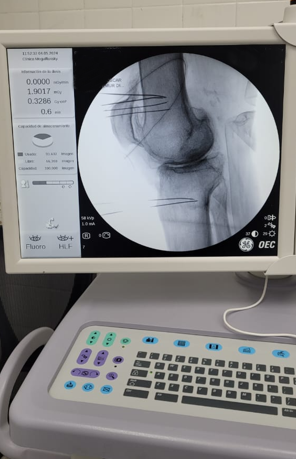

Por la morbimortalidad de la cirugía, se procede a realizar en Tidol un tratamiento con radiofrecuencia, debido al dolor intenso que le impedía la marcha.

Luego del procedimiento, el paciente deja de tomar los calmantes que se encontraba tomando para el dolor intenso y mejora su patología dolorosa.